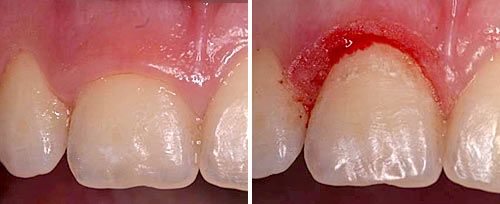

Frenectomy Treatment

Courtesy of: Giovanni Olivi, MD, DDS

Laser source: Er:YAG (2940 nm)